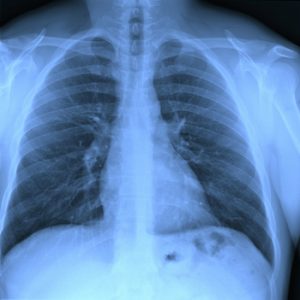

If it is suspected that the diaphragm is not working correctly, there are a number of tests that may be performed. These include chest x-rays, blood tests, phrenic nerve stimulation testing, MRI and ultrasound. A physician will be able to give specific information on the best test for your specific symptoms.